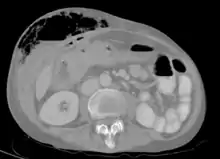

Abdominal CT scan with right colocutaneous fistula and associated subcutaneous pneumatosis | |